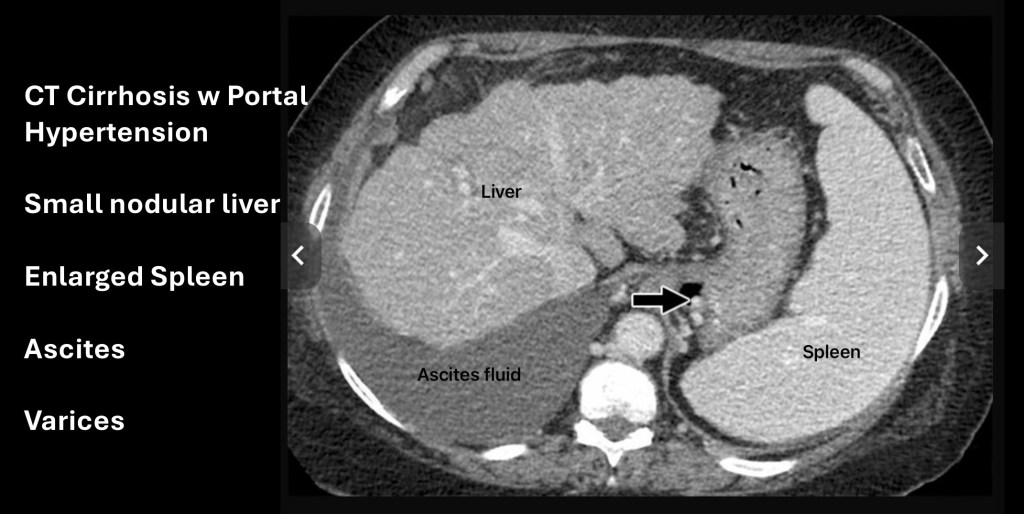

This is a CT scan of the upper abdomen following IV contrast in an individual with cirrhosis. To the left on the image (anatomic right) the liver is smaller than normal. The liver has a nodular contour. The margins are normally smooth. This is due to scar tissue and volume loss.

Just adjacent to the liver toward the bottom of the image is darker grey material. This is ascites, a buildup of free fluid in the abdomen which may need to be drained periodically if persistent.

On the opposite side is the spleen which is enlarged (splenomegaly). It should be smaller than the liver.

The arrow points to small rounded bright structures. These are varices at the lower esophagus where it joins the stomach.